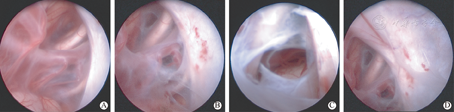

对于囊壁的剥离度是涉及到手术疗效的焦点,过度剥离产生损伤也直接影响愈后。目前多数学者赞同不要求全剥囊壁只要能达到与脑池和蛛网膜下腔充分沟通[6]、术中尽可能减少出血。对于中颅窝底囊肿,内侧中线部位为鞍上池,对此内镜在锁孔技术、液态环境、多角度和深入浅出的手术操作环境下[14]具备优势。本组均采用内镜直视下对鞍上池进行造瘘和开窗,未主动剥离脑表面蛛网膜,术后随访结果显示疗效满意,72.2%患儿在平均10个月达到囊肿消失(图2:术前、术后1年),且89.5%缩小一半以上(其中Ⅱ型为90.8%、Ⅲ型为87.5%)。内镜手术中无开颅术需排尽囊液所造成颅低压之虑,持续平衡液灌流保持颅压相对稳定和视野的清晰。本组患儿囊肿Ⅰ~Ⅲ型,故因颞叶推移程度不一,内镜进入囊内有三种途径,以使进入囊后能直接正对观察到鞍上池。所有患儿鞍上池呈膜状封闭(图2A),根据鞍上池显露血管神经间隙程度选择视神经前后间隙、颈内动脉-动眼神经间隙、动眼神经后间隙进行膜上开窗,用微型剪刀和球囊扩张相结合最大程度将血管神经间隙打开(图2B),电凝收缩飘动囊壁和窗缘。动眼神经-脑干间存在间脑膜者需继续分离和打开(图2C),直至各间隙内清晰见同侧甚至对侧视神经及颈内动脉各分支、动眼神经及基底动脉、脑干等结构。术中如见中颅窝底囊壁随颅压下降和水流冲击后漂浮者需将之切除,以防止出血和飘落囊壁封堵造瘘口(图2D),如囊壁无松动则不主动强求剥离。囊肿破裂者可见壁层塌陷呈不同程度纤维变、增厚及含铁血黄素沉着,可大部分去除。术中开窗时需精细操作和及时球囊压迫出血点,所有病例未出现不可控的出血。4例囊壁病理为室管膜囊肿,分析其影像与蛛网膜囊肿无异,术中发现囊壁较蛛网膜囊肿厚、韧,囊壁上血管分支较多,术中较易出血,操作上尽量避免牵扯。1例患儿囊压极高见动眼神经压至后岩床上,囊壁韧,打开囊壁见动眼神经周围纤维网状粘连,予分离时存在损伤,术后有动眼神经麻痹症状,但2个月后眼裂和眼球恢复正常。